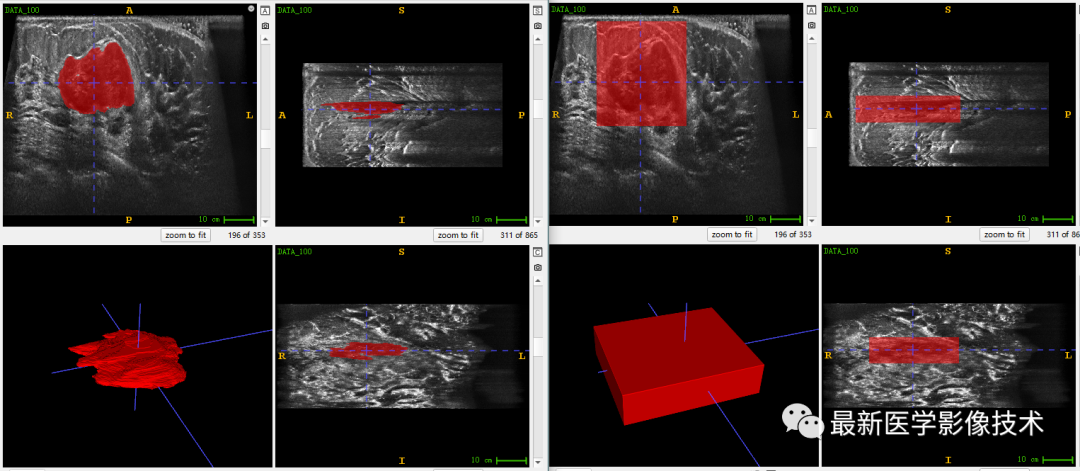

乳腺肿瘤分割采用两阶段分割网络,第一个网络进行粗分割定位肿瘤位置,第二个网络进行精分割得到肿瘤精确轮廓,然后在根据精分割mask和对应ROI图像进行良恶性分类。具体实现可以参考这篇文章TDSC-ABUS2023——2023 年自动化 3D 乳腺超声 (ABUS) 的肿瘤检测、分割和分类挑战.

验证集分割和检测部分结果如下所示。